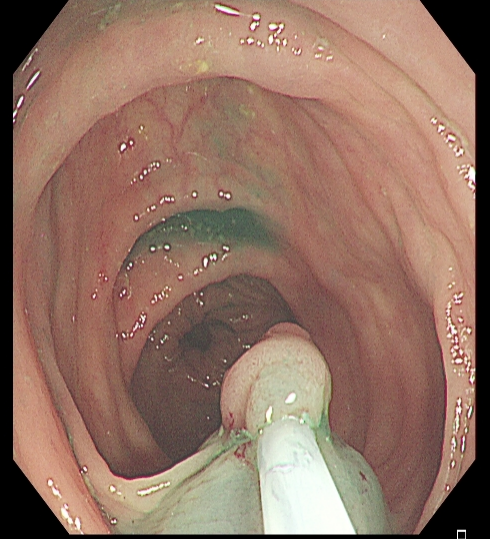

适用于不同大小隆起型病变Ⅰp型、Ⅰsp 型以及小型(<2 cm)Ⅰs型(具体分型标准可参照内镜发现消化道早癌,分型太多不知道怎么判断?这篇文章讲清楚了)病变的切除。小型Ⅰp型病变,圈套切除相对简单,可采用冷或热圈套切除,切除时应在保证完整切除病变同时,保留一定长度的蒂部或与肠壁保持一定距离,收紧圈套后,应抖动圈套器,观察有无周围正常肠黏膜一并套入,防止损伤肠壁。

图2 小型Ⅰsp 型病变热圈套切除示意图